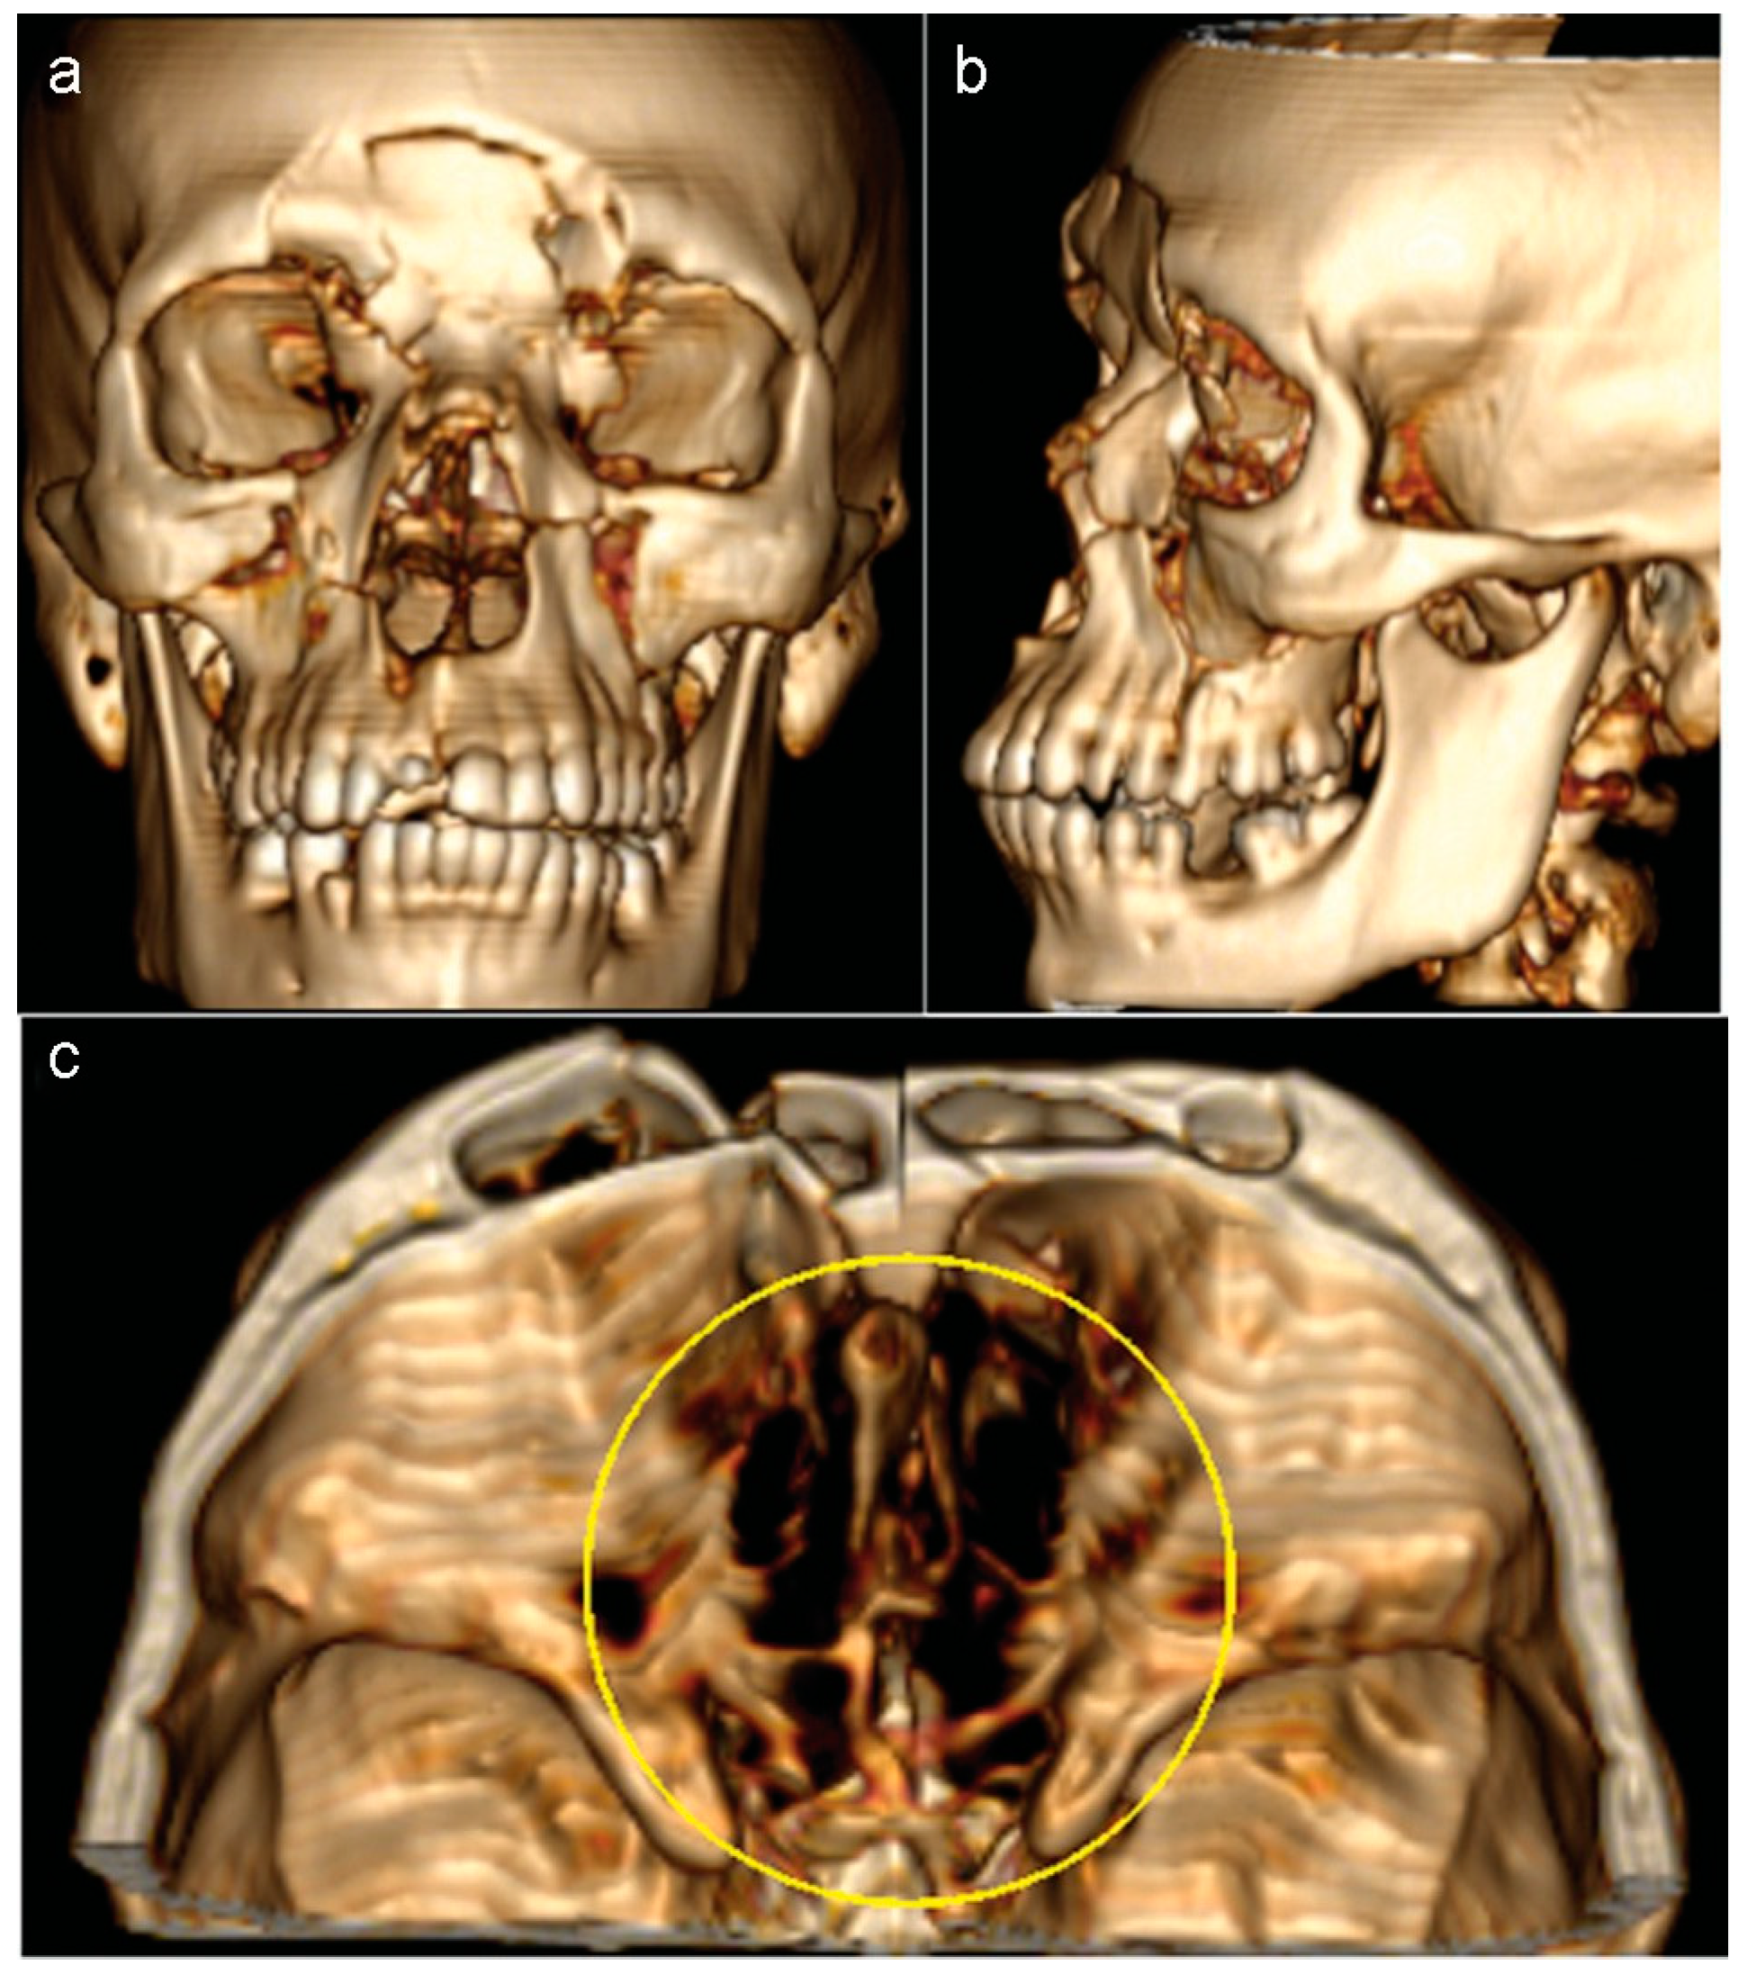

After 18 days, the same patient returned with pulsatile headache, dizziness, and nausea. Besides this clinical sign, a new CT scan revealed a large encephalocele associated with an extensive defect of the anterior skull base (Figure 5a–d).

Figure 5. (a and b) Eighteen days after the procedure, the patient returned and a new CT scan revealed a large encephalocele. The protrusion of the brain through the nasal cavity was associated with an extensive defect of the anterior skull base. (c and d) Three-dimensional volume rendering images showed that the osseous defect had increased after first surgery.